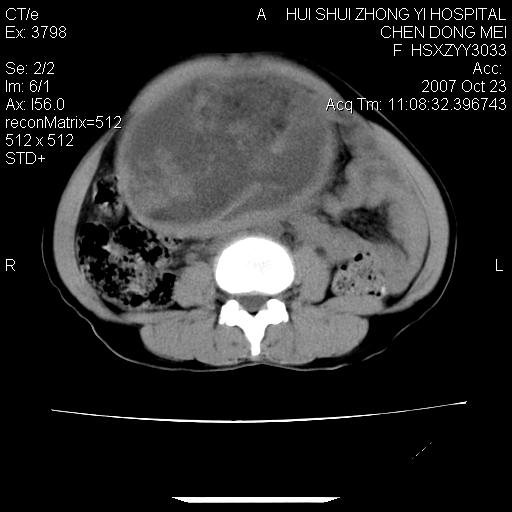

标题: CT10156:女.43岁,发现中下腹部包都块2年

发现中下腹部包都块2年。2年来月经不规律。

腹腔巨大软组织密度影,边缘光滑,包膜完整,内囊变坏死。腹膜后及盆腔内淋巴结肿大。结合病史考虑卵巢癌可能性大。

病灶内可见脂肪密度影,考虑畸胎瘤可能性大

病变巨大,呈囊实性改变,包膜较厚且完整,内见分膈,周围脏器明显受压移位,病变与左侧附件关系密切,考虑来源左侧附件的囊腺瘤,不除外癌变可能;畸胎瘤可能性较小。

病变巨大,呈囊实性改变,包膜较厚且完整,内见分膈,周围脏器明显受压移位,病变与左侧附件关系密切,考虑来源左侧附件的囊腺瘤,盆腔内见肿大淋巴结,不除外癌变可能。